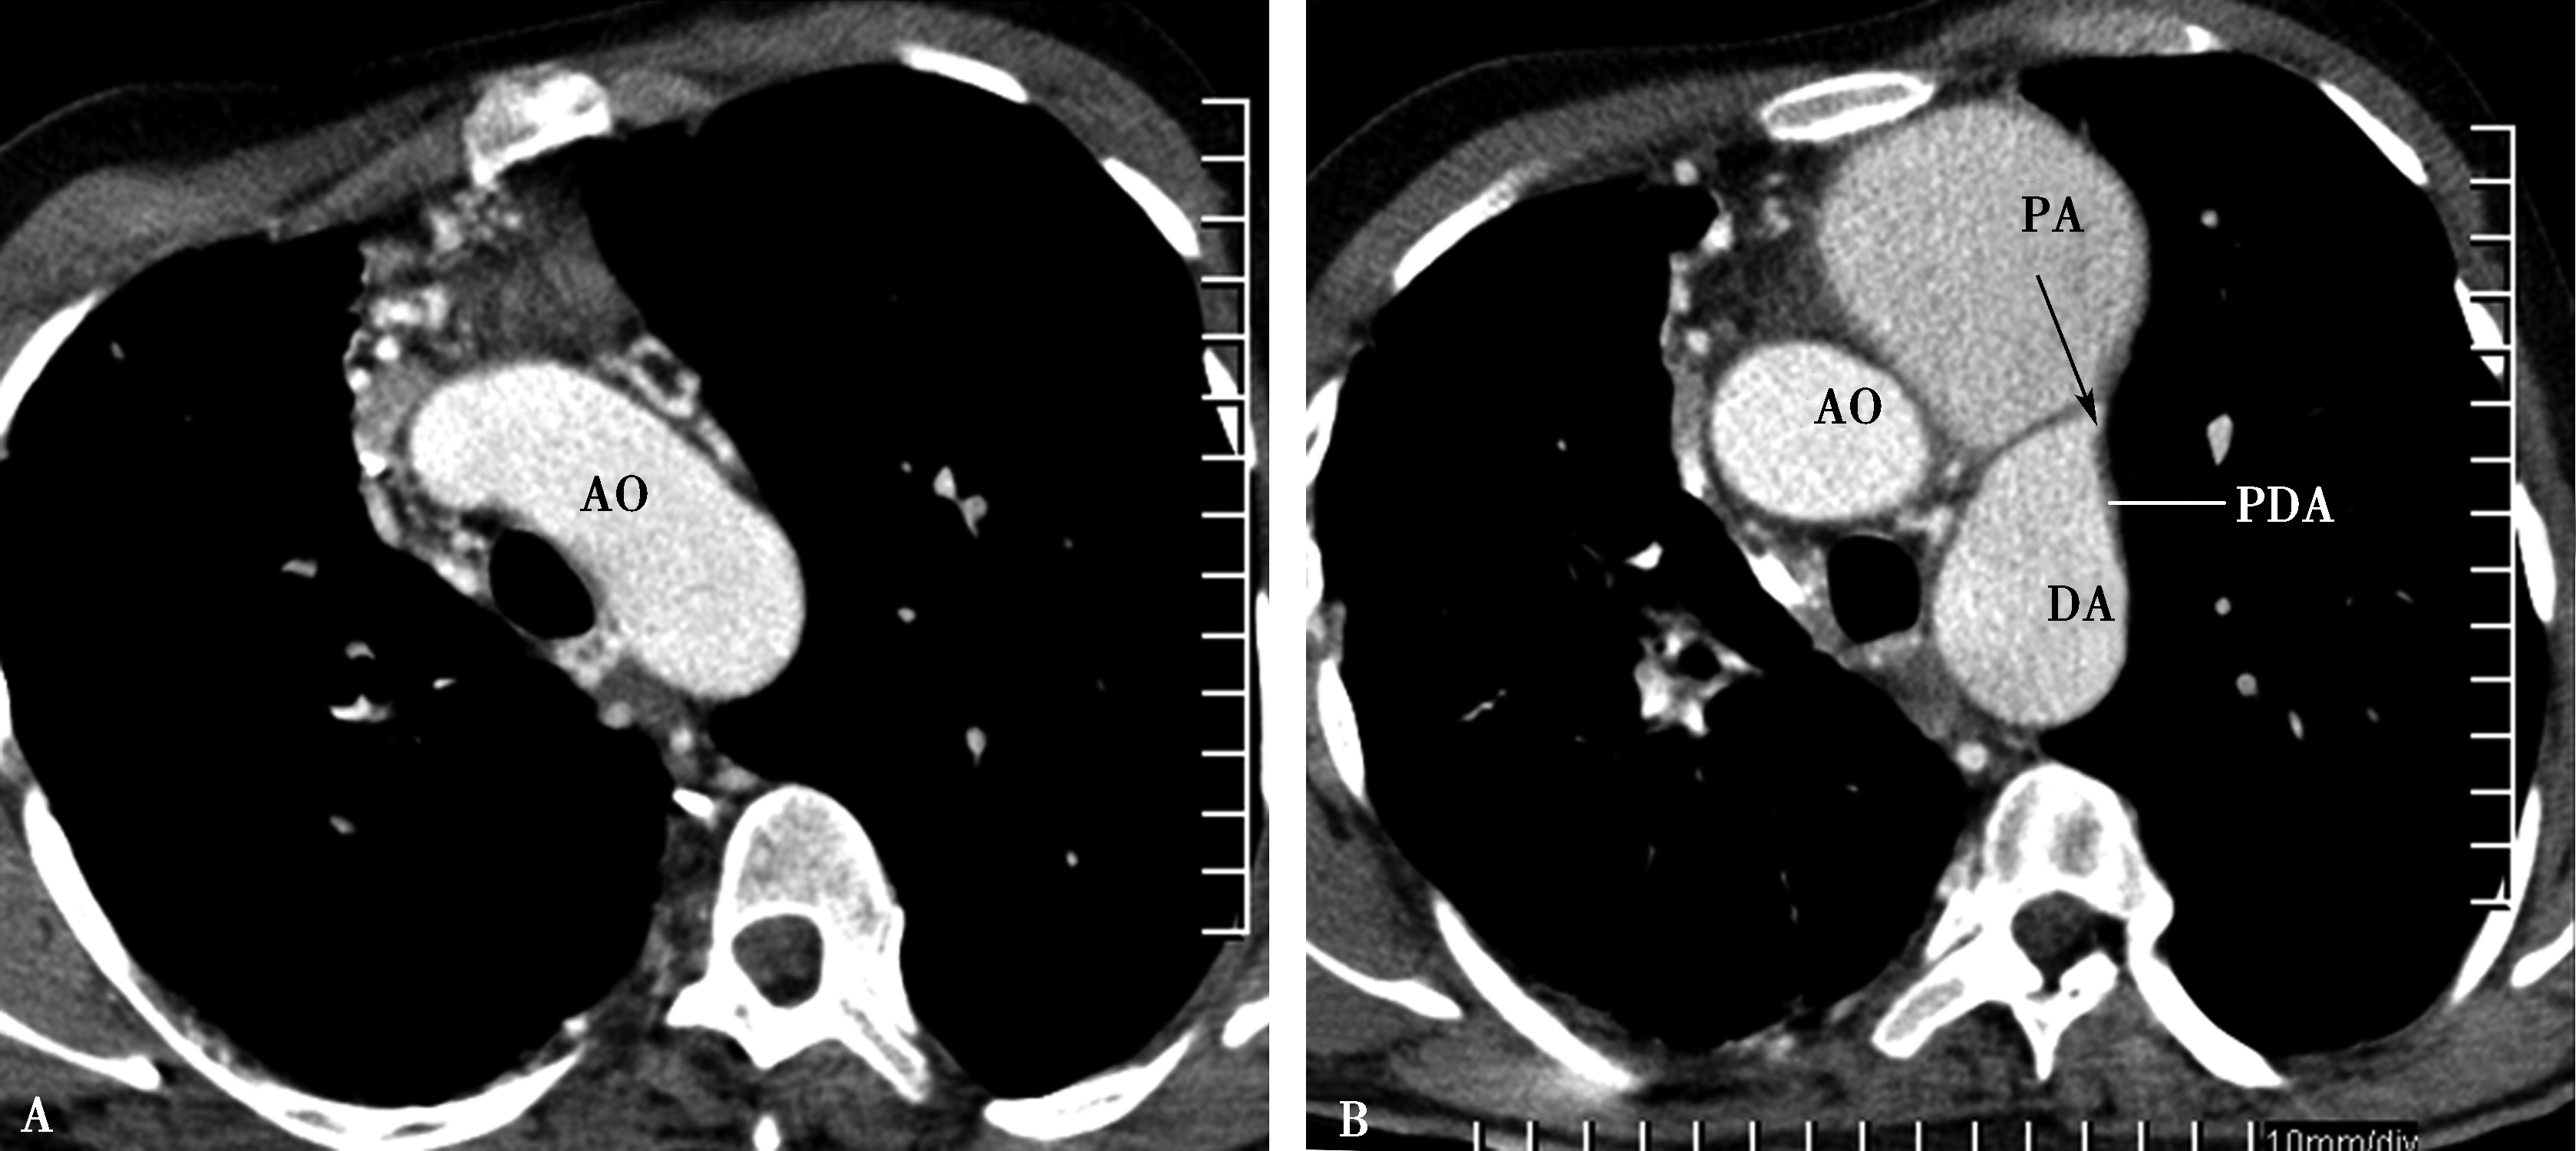

图8-8-2 男,33岁,肺动脉夹层(横断图像)

先天性心脏病:右肺动脉缺如、动脉导管未闭、肺动脉高压、肺动脉夹层(B,C,D↑)。AO:升主动脉;PA:主肺动脉;PDA:动脉导管未闭;DA:降主动脉